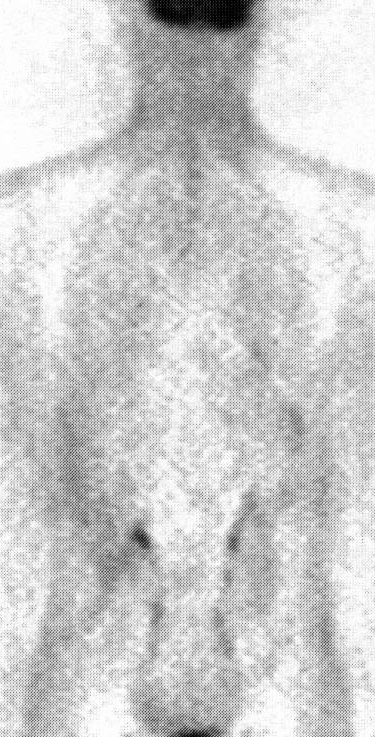

Рис. 4

ри обследовании больных дифференцированным раком щитовидной железы с повышенным уровнем опухолевого маркера (тиреоглобулина) на фоне отрицательного результата сканирования «всего тела» с 131I, наиболее важной задачей ПЭТ является выявление рецидивов. По мнению большинства исследователей ПЭТ является эффективным методом выявления йод-негативного метастатического поражения шейно-надключичных, медиастинальных лимфоузлов и легких (рис. 4). Имеются сообщения об успешном применении ПЭТ у больных раком щитовидной железы.

Рис. 4. ПЭТ-визуализация метастазов папиллярного рака щитовидной железы в лимфоузлы шеи у больного, ранее перенесшего 2 шейные лимфодиссекции.